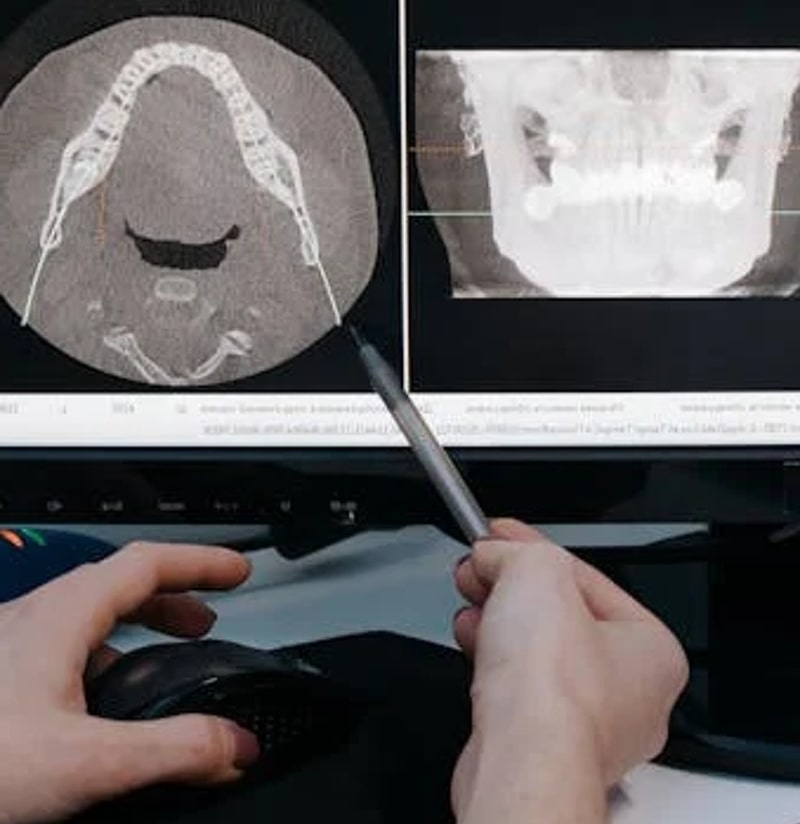

We Provide a Full Range

of Dental Services

At Parkway Dentistry, we offer a comprehensive range of dental treatments to promote optimal oral health, enhance your smile, and boost your confidence. From general family dentistry to oral rehabilitation and complete cosmetic smile makeovers, our team – led by Dr. Pio Modi – provides expert care tailored to your needs.